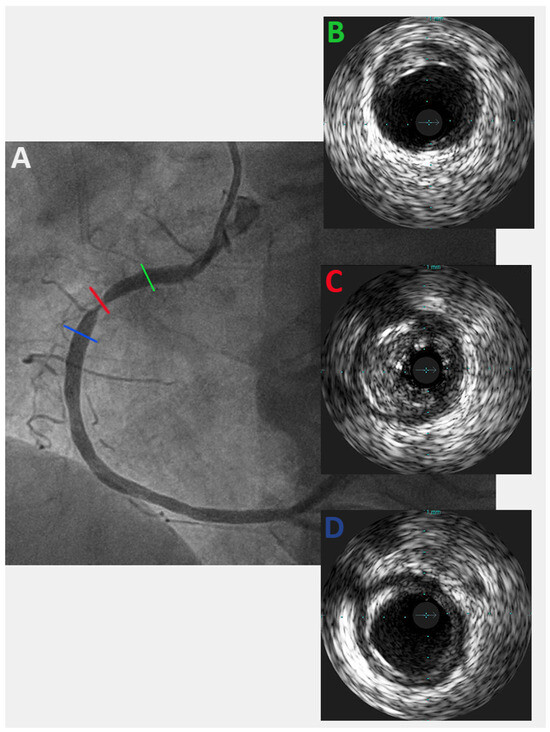

When performing revascularisation of a chronic total occlusion, contralateral injection is essential to visualise the distal bed of the occluded vessel, adding to procedural success. Here we describe a case of antegrade recanalisation of a left anter...